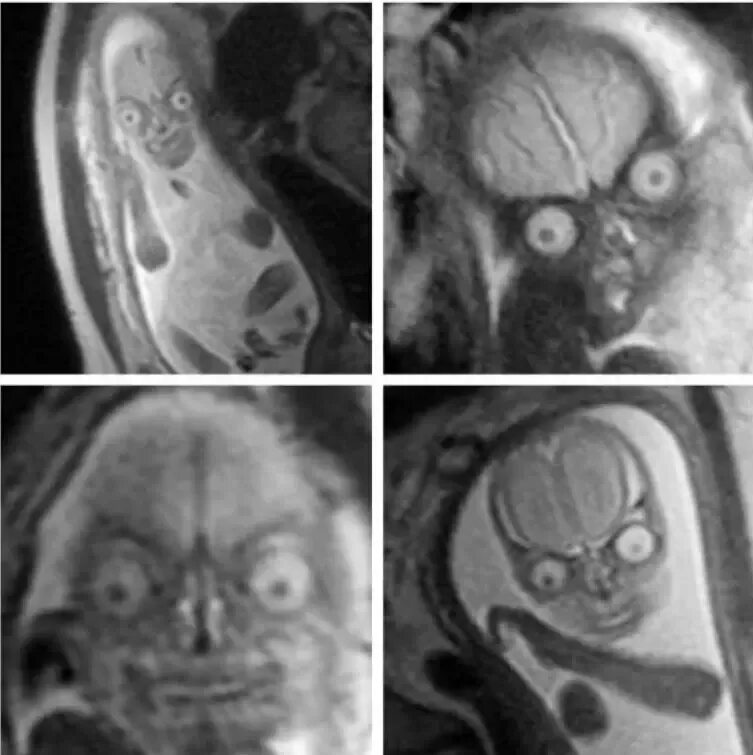

Мрт беременной